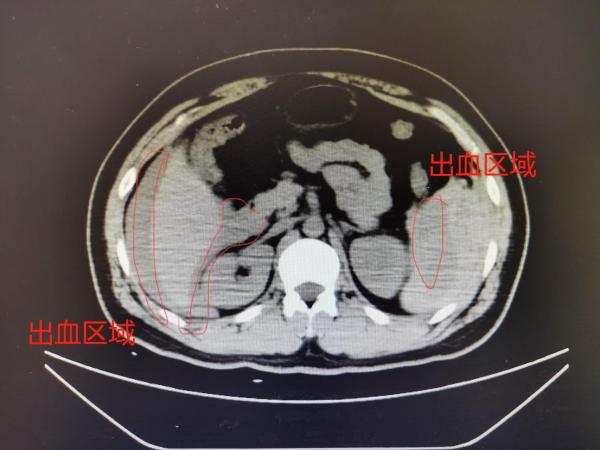

随着小哥的苏醒,大家才了解到他的意外是怎么发生的。原来,这位快递员当天在为封控小区运送生活必备物资,已经连续奋战工作超过12小时。14日晚上下着雨,小哥又处于疲劳状态,骑助动车时不慎滑倒,摔在路边的台阶上,这才导致腹部外伤、脾破裂、腹腔内大出血,被送至新华医院急诊。